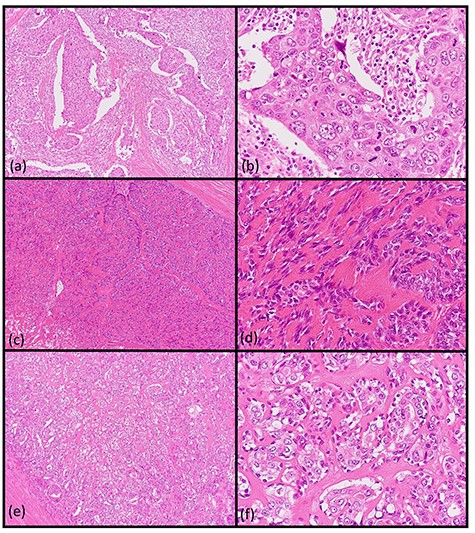

A 62-year-old man presented to our hospital after detecting a mass in the right parotid gland. He had no personal or family history of malignancy. On physical examination the mass was 5.0 × 5.0 cm in size with poor mobility. Computed tomography revealed a tumor (5.1 × 5.0 cm) within the right parotid gland that was enhanced by contrast (Fig. 1a). The tumor had an irregular shape with calcifications, a low-density area and the boundary between the tumor and surrounding tissues was indistinct. A malignant tumor of the right parotid gland was suspected, thus tumor resection with lymph node dissection was performed. The cut surface of the tumor was yellow–white with hemorrhage and necrosis (Fig. 1b). The tumor boundaries were ill-defined. The proliferation of three morphologically-different tumor cells was demonstrated on histopathologic examination. First, the cell type was atypical with abundant granular eosinophilic cytoplasm, large nuclei with coarse chromatin and prominent nucleoli. The cells were proliferative and invasive with duct-like, glandular and solid patterns (Fig. 2a and b). Frequent mitotic activity and necrosis were evident. The cells had the characteristics of a salivary duct carcinoma (SDC). Second, the atypical spindle-to-epithelioid cells with a clear cytoplasm were proliferative and invasive with trabecular, tubular and solid patterns (Fig. 2c and d). The stroma was hyalinized. The cells had the characteristics of a myoepithelial carcinoma (MC). Third, atypical duct-like structures were composed of two distinct cell layers. The inner layer was comprised of cuboidal cells with eosinophilic cytoplasm and round enlarged nuclei and the outer layer consisted of cells with clear cytoplasm and oval nuclei (Fig. 2e and f). The cells had the characteristics of an epithelial-myoepithelial carcinoma (EMC). In addition, the shape of the inner layer cell nuclei was similar to SDC. These three tumor types invaded the surrounding tissues and appeared to be a mixture of cells with reciprocal transfer in the same area (Fig. 3). Immunohistochemistry was performed using the Dako Envision+ System with dextran polymers conjugated to horseradish peroxidase (Dako, Glostrup, Denmark). The following primary antibodies (all purchased from Dako) were used: AR (AR441); αSMA (1A4); cytokeratin (AE1/AE3); EMA (E29); GCDFP-15 (23A3); polyclonal HER2; Ki-67 (MIB-1); p53 (DO7); p63 (DAK-p63); polyclonal S-100 and WT1 (6F-H2). The results of immunochemistry staining are shown in Table 1. Briefly, most of the SDC cells were positive for cytokeratin AE1/AE3, EMA, AR (Fig. 4a), HER2 (Fig. 4b) and p53. In contrast, most of the MC cells were positive for p63 (Fig. 4c), αSMA, S-100 (Fig. 4d) and WT-1, and weakly positive for cytokeratin AE1/AE3. Most of the EMC inner layer cells were positive for cytokeratin AE1/AE3 (Fig. 5a), EMA, and p53, and weakly positive for AR and HER2 (Fig. 5b). Most of the EMC outer layer cells were positive for p63, αSMA, S-100 and WT-1, and weakly positive for cytokeratin AE1/AE3 (Fig. 5a). In the mixed cell area, most of the EMC inner layer cells were positive for cytokeratin AE1/AE3, most of the EMC outer layer cells and MC cells were weakly positive for CK AE1/AE3 (Fig. 5c), and most of the EMC outer layer cells and MC cells were positive for p63 (Fig. 5d).

Histopathologic findings of the parotid tumor. (a and b: hematoxylin and eosin staining, ×40 and ×400) The cell type was atypical with abundant granular eosinophilic cytoplasm, large nuclei with coarse chromatin and prominent nucleoli. The cells were proliferative and invasive with duct-like, glandular and solid patterns. (c and d: hematoxylin and eosin staining, ×40 and ×400) The cell type was an atypical spindle-to-epithelioid cell with clear cytoplasm that was proliferative and invasive with trabecular, tubular and solid patterns. (e and f: hematoxylin and eosin staining, ×40 and ×400) The cell type was an atypical duct-like structure comprised of two distinct cell layers. The inner layer consisted of cuboidal cells with eosinophilic cytoplasm and round enlarged nuclei and the outer layer consisted of cells with clear cytoplasm and oval nuclei.